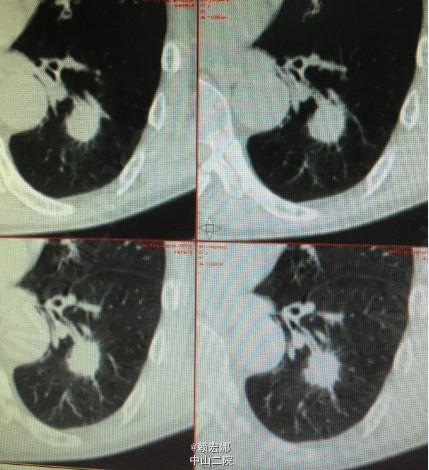

患者,男,67岁,咳嗽、咳痰1年余。外伤后查体发现左下肺占位1周余。

胸廓未见异常,胸骨无压痛,乳房正常对称。呼吸运动未见异常,肋间隙未见异常,语颤未见异常。叩诊清音,呼吸规整,双肺呼吸音清晰,双肺未闻及干湿性啰音,无胸膜摩擦感。心前区无隆起,心尖搏动未见异常,心浊音界未见异常。浙江省永嘉县人民医院胸片提示左下肺结节 ,CT提示左下肺占位 ,考虑周围型肺癌可能。我院PET-CT:1、左下肺背段结节状高代谢病灶,考虑为左肺癌;2、纵膈内多发淋巴结炎性增生;双肺门及纵膈内未见恶性肿瘤征象;3、颅内双侧侧脑室旁脑白质变性;脑桥右侧陈旧性脑梗塞灶;右侧筛窦轻度炎症;双侧颈部及双侧腋窝多发淋巴结炎性增生;4、双肺尖多发陈旧性炎症,双肺尖多个小肺大泡;双上肺肺气肿;5、肝左内叶小囊肿;左肾小囊肿;前列腺钙化灶;6、全身其他部位未见明显异常。

患者肺癌诊断明确,术前检查未见明显禁忌症,胸腔镜下行左下肺癌根治术,手术顺利,术后病理:1、(左下肺)浸润性肺腺癌,实体为主型;2、支气管及肺切缘未见癌残留;3、(5 7 9 10 11组)淋巴结未见癌转移(0/4 0/5 0/2 0/1 0/1).术后予重症监护,抗感染、营养支持等对症支持治疗。